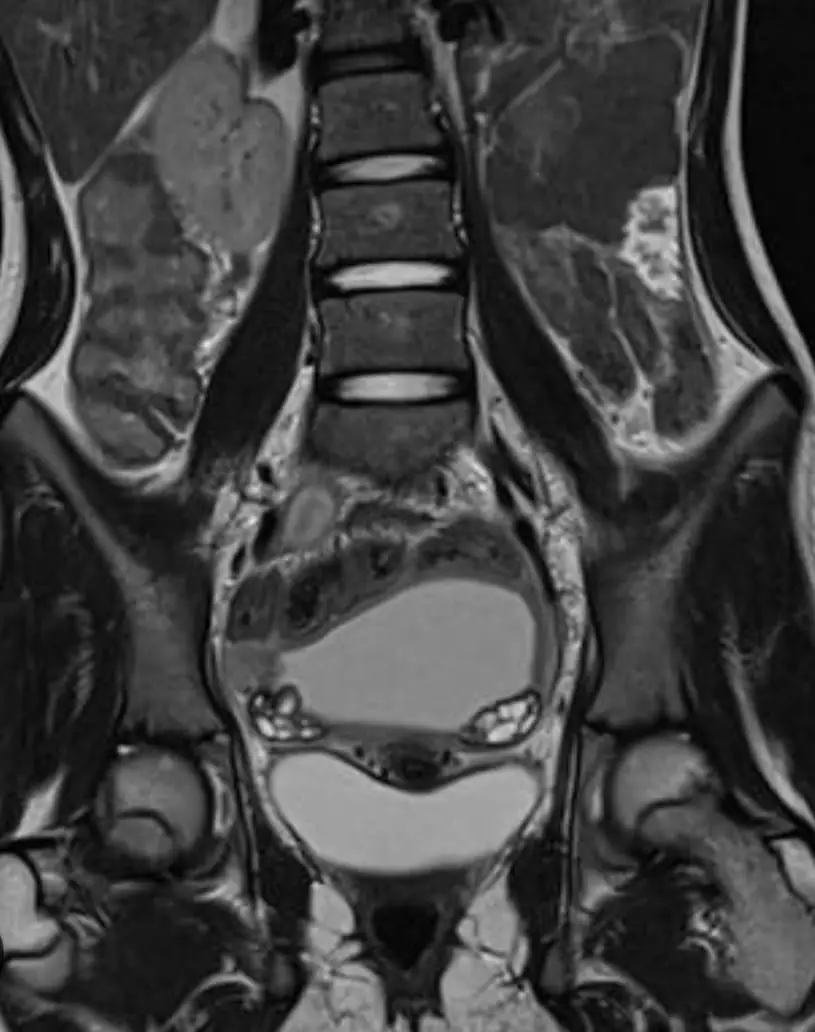

МРТ малого таза у мужчин

Визуализация предстательной железы, семенных пузырьков, мочевого пузыря, лимфоузлов, прямой кишки.